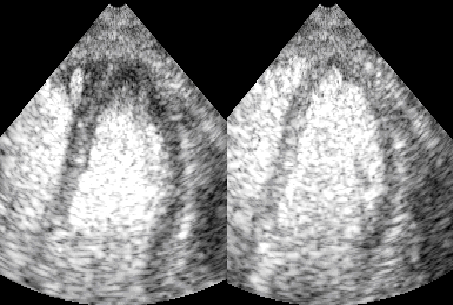

O padrão visual da perfusão miocárdica foi considerado anormal quando o contraste, em repouso, distribuiu-se de forma heterogênea nos segmentos das paredes do ventrículo esquerdo ou, como mais freqüentemente observado, se seguiu de diminuição ou mesmo da falta de intensificação do contraste, em segmentos normais em repouso, ao final da administração do nitroprussiato de sódio (Fig. 2).

Imagem de ecocardiograma exibindo um corte 2 câmaras apical contendo perfusão miocárdica normal em repouso (esquerda) com perfusão anormal após infusão de nitroprussiato de sódio (direita)

Figura 2 – Corte 2 câmaras apical - Perfusão miocárdica normal em repouso (esquerda). Perfusão anormal após infusão de nitroprussiato de sódio (direita)